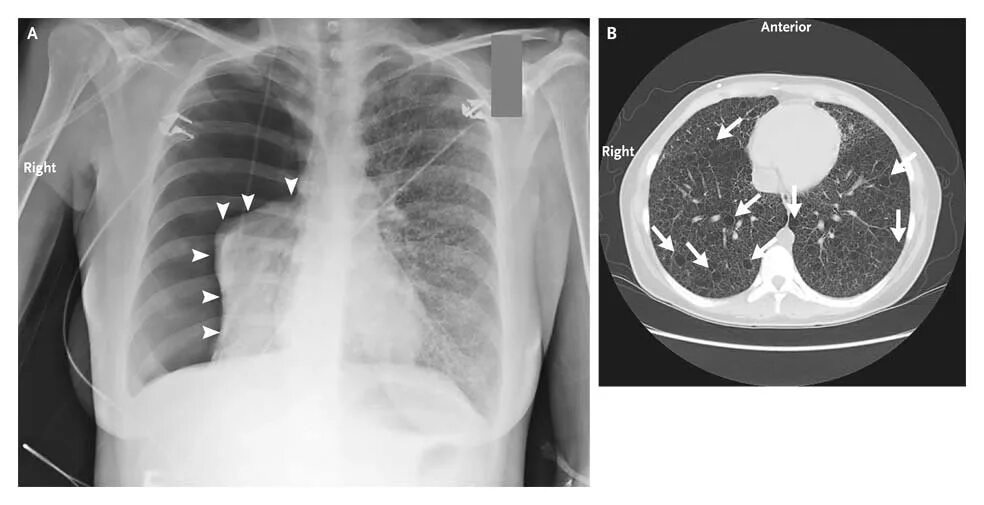

Туберкулезный склероз